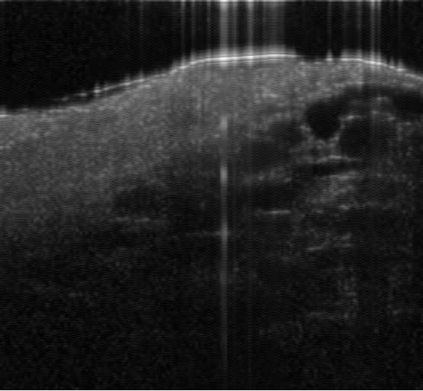

Coronary artery disease (CAD) is a cardiovascular condition with high morbidity and mortality. Intravascular optical coherence tomography (IVOCT) has been considered as an optimal imagining system for the diagnosis and treatment of CAD. Constrained by Nyquist theorem, dense sampling in IVOCT attains high resolving power to delineate cellular structures/ features. There is a trade-off between high spatial resolution and fast scanning rate for coronary imaging. In this paper, we propose a viable spectral-spatial acquisition method that down-scales the sampling process in both spectral and spatial domain while maintaining high quality in image reconstruction. The down-scaling schedule boosts data acquisition speed without any hardware modifications. Additionally, we propose a unified multi-scale reconstruction framework, namely Multiscale- Spectral-Spatial-Magnification Network (MSSMN), to resolve highly down-scaled (compressed) OCT images with flexible magnification factors. We incorporate the proposed methods into Spectral Domain OCT (SD-OCT) imaging of human coronary samples with clinical features such as stent and calcified lesions. Our experimental results demonstrate that spectral-spatial downscaled data can be better reconstructed than data that is downscaled solely in either spectral or spatial domain. Moreover, we observe better reconstruction performance using MSSMN than using existing reconstruction methods. Our acquisition method and multi-scale reconstruction framework, in combination, may allow faster SD-OCT inspection with high resolution during coronary intervention.